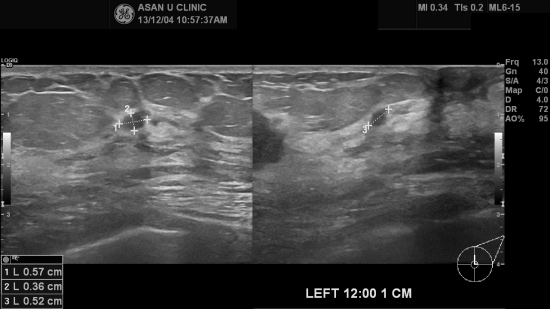

아산유외과 개원후 41번째 유방암진단.

만져지는 유방불편감있어 조직검사의뢰된 분으로

40대가 체 안되신 분입니다.

1.9cm, 0.5cm, 0.4cm 의 세개의 혹이 좌측 유방 12시방향에 흩어져 있었고

조직검사상 침윤성 유방암으로 확인되었습니다.